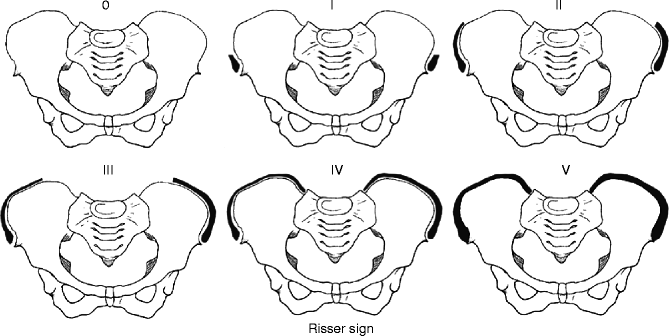

장골 골단의 골화는 Anterior Superior Iliac Spine 에서 시작하여 Posterior Superior Iliac Spine 까지 진행하게 됩니다. 골골화가 4단계 까지 진행된 후에 완전히 골화가 진행되어 5단계가 되게 됩니다.

각 단계마다 확인해보면 1단계는 25% 이하, 2단계는 25~50%, 3단계는 50~75%, 4단계는 75~100% 골화가 진행되는 것으로 분류하고, 5단계는 장골에 유합되는 것입니다.

골단은 2차 발생중심으로, 여아 14.25세 남아 15.4세에 나타나서, 청소년기의 골성장을 유추해 볼 수 있습니다.

Risser 4가 된 경우네는 척추의 성장이 종결되며

Risser 5에서는 더이상 뼈의 성장이 일어나지 않습니다. 고로 키가 더이상 크지 않을 것을 유추할 수 있습니다.